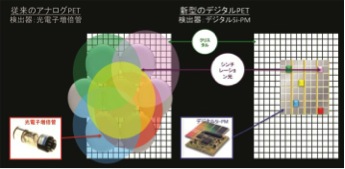

従来のPET装置の検出器には、アナログ素材で真空管の一種である光電子増倍管(PMT:Photo- multiplier Tube)が長らく用いられてきた。Vereos PET/CTでは、検出器にデジタル半導体を採用することで光電子増倍管を用いたPET装置に比べ検出精度を大幅に向上させ、アナログ由来のノイズ混入を排除することで、画像の分解能、システム感度と高い定量性を獲得した。

2.1to1カップリング方式

これまでの検出方式では、アンガーロジック(Anger-Logic)型と呼ばれる、クリスタル1個につき複数の検出器(1:7や検出器によっては1:数十)を用いて、数学的に当該シンチレーション光の重心演算により位置を特定する方式が主流だった。この方式では画像の歪みと空間分解能の劣化が課題として残っていた。デジタルSi−PM検出器ではクリスタル1個と半導体の受光面(素子)を完全に1:1で対応させることで、画像の歪み補正と位置演算を不要とし、クリスタルの寸法にほぼ等しい空間分解能を達成している。